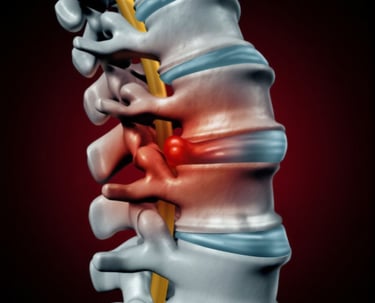

Slipped Disc Surgery

A surgical procedure that removes the herniated portion of a spinal disc that is pressing on nearby nerves. By relieving nerve compression, it alleviates pain, numbness, and weakness in the back, neck, or extremities—restoring mobility and quality of life for patients who have not responded to conservative treatments.